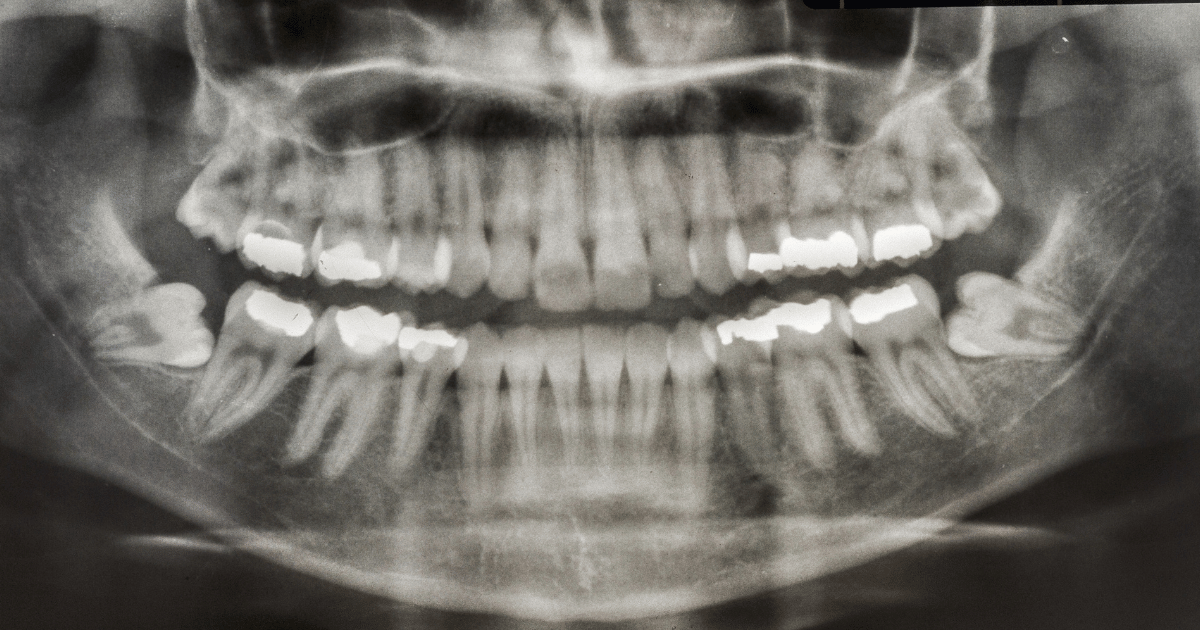

腫れ・出血・痛みのピークと自然な回復の流れ

腫れや痛みは、親知らずを抜いた直後よりも2〜3日目がピークになることが多いです。

これは、体が治そうとする反応のひとつであり、異常ではありません。

腫れは、抜いた側の頬がふくらんだり、口が開きにくくなったりします。痛みも、じんじんと響くような感覚が出ることがありますが、処方された痛み止めを使えば多くは乗り切れます。

例えば、アイスノンなどで短時間ずつ冷やすと、腫れの拡大を防ぐ助けになります。ただし、冷やしすぎると血行が悪くなり、逆に回復が遅れるため注意が必要です。

出血も、ティッシュに少しにじむ程度なら心配ありません。強く口をすすいだり、患部を触ったりせず、回復を妨げないように過ごしましょう。